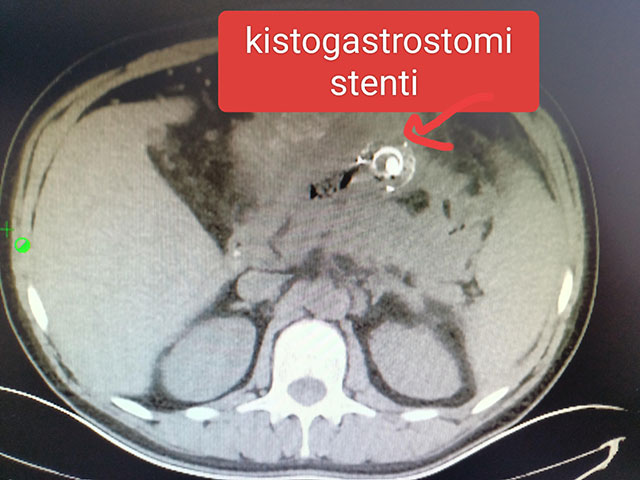

Ağır pankreas iltihaplanmasına bağlı ateş ve ağrıya endoskopik çözümProf.Dr. Yücel ÜSTÜNDAĞ

Pankreas iltihaplanması bizim alanımıza ait en sık karşılaştığımız sorunlardan biridir. Çoğunlukla safra kese taşlarının ana kanala düşmesi sonucu veya alkol kullanımı ile ilişkili olan bu durum, şiddetli karın ağrısı, bulantı-kusmaya neden olur. Genelde bu hastalar basit müdahalelerle kısa sürede toparlayabilirler. Ancak hastaların %10-20’sinde hastalık daha şiddetlidir ve hayati riskler yaratabilir. Bu durumda ki hastaların genel durumları daha sıkıntılı, ağrılı ve ateş bulantı ağızdan beslenememe sorunları olur. Karın içinde ve akciğerde yoğun iltihaplı sıvı birikebilir ve bu içerik ölü pankreas dokusu, ölü yağ dokusu içerir. Kolay enfekte olan bu sıvı birikimleri hastalar için hayati riskler yaratırlar ve hastanede yatış süresini uzatabilirler. Bu sıvı birikimleri enfekte iseler ya cerrahi yoldan ya da perkutan kateterler ile (ciltten yerleştirilen tüpler) ile boşaltılabilir. Diğer bir yöntem ise enfekte olan pankreas iltihaplı alanın endoskopik olarak mideye boşaltılması ve mide barsak sistemi ile vücuttan uzaklaştırılmasıdır.

Ciddi pancreas iltihabı ile gelen hastalarımıza endoskopik ultrasonografi cihazını kullanarak, yüksek işlem etkinliği ve minimal zarar potansiyeli ile oldukça önemli bir tedavi imkânı sağlayabilmekteyiz. Sağlıcakla kalın ve düzenli / sık alkol tüketiminden uzak durun.